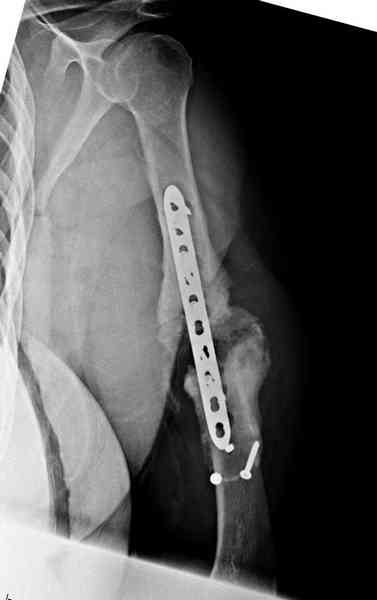

Хотя сам не стороннник применения более массивных

имплантов для плеча, но для этого случая сделали

исключение. На снимке 4А диаметр мягких ткани около 20 см, при весе больной более 135 кг, и также выступление Андрея Волны подстегнуло к применению более массивной 4.5 мм локинг пластины.